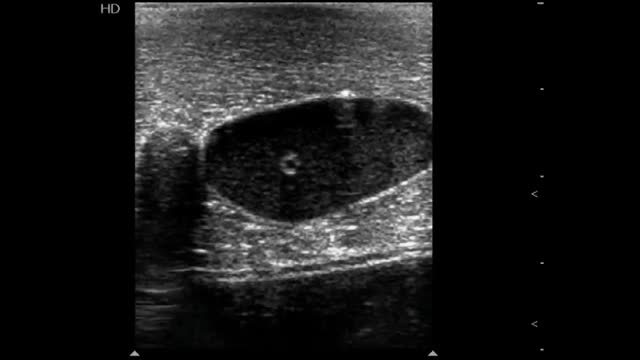

In the short axis, the veins are more oval than round, have an anechoic content, their walls are thin, they are fully compressible and, lastly, they are not pulsatile. On the contrary, the arteries are round, also have an anechoic content, have a thicker wall in comparison with veins, are poorly compressible and, lastly, they have pulsatility2,7 (Fig. 3A).

Ultrasonographic (US) appearance of the vessels. (A) Vessels in short axis, v: vein; a: artery; (B) vein (v) in long axis; (C) artery (a) in long axis; (D) vein flow demonstrating phasicity at spectral Doppler; (E) arterial flow demonstrating pulsatility at spectral Doppler; (F) differences between a superficial vein (sv, above deep fascia and muscle) and a deep vein (dv).

In the long axis, the vessels appear tubular (Fig. 3B and C). Valves can sometimes be observed in the veins, with the corresponding normal opening and closing movements. Arteries lack valves. In some cases, when a proximal tourniquet is applied in the veins, stagnant blood, also called rouleaux, can be observed as internal mobile echoes within the vein, fully cleared when compressed with the transducer.

Using color and spectral Doppler, veins normally have a phasic flow (Fig. 3D) (having augmentation with distal compression), whereas arterial flow is pulsatile (Fig. 3E).

Superficial veins are found above the deep fascia and muscle, and they are not accompanied by arteries. On the contrary, deep veins are located below the deep fascia and are always accompanied by arteries (and nerves) in the neurovascular bundle (Fig. 3F).